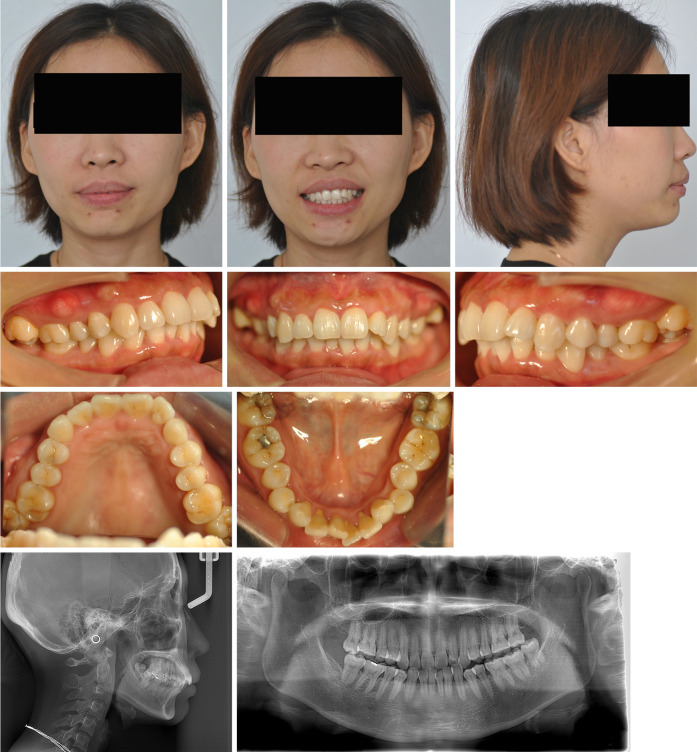

使用无托架的透明矫正器治疗双侧磨牙深覆咬合并颊交叉咬:一个病例描述。

Management of bilateral molar deep overbite with buccal crossbite using bracket-free clear aligners: a case description.